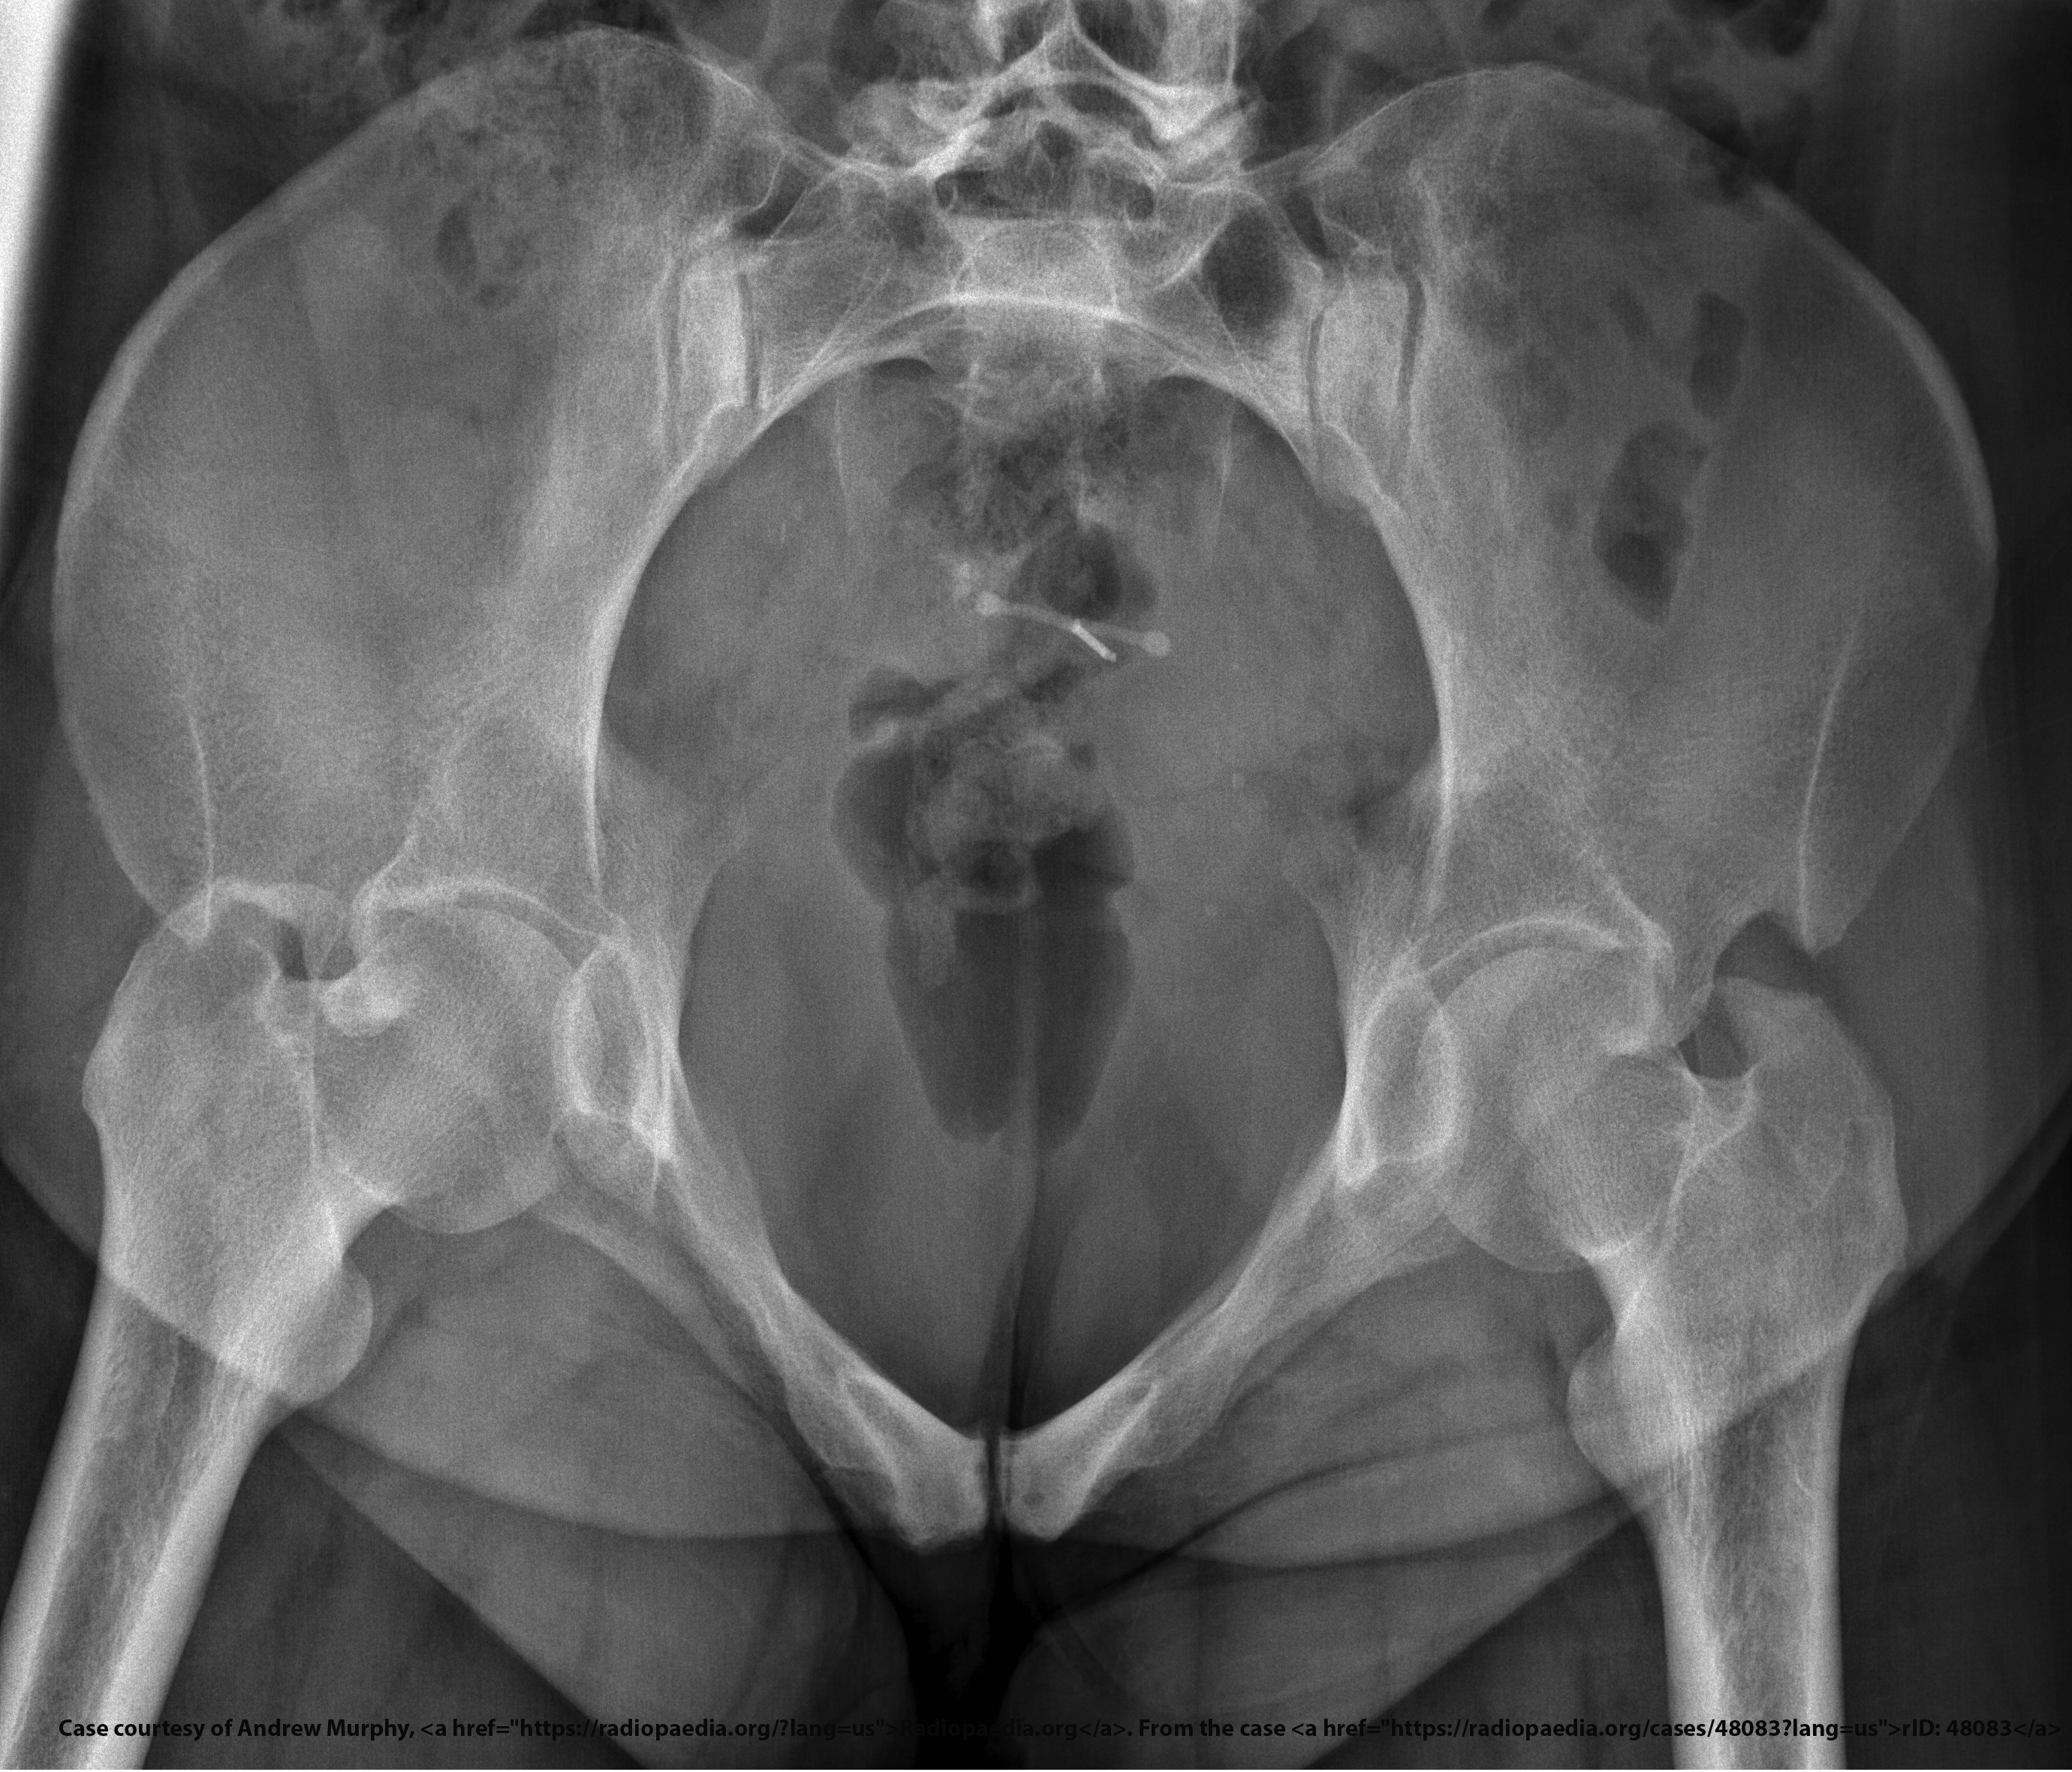

What is the CR angle for an AP axial SI joint projection (male)?

30° cephalad.

What is the CR angle for an AP axial SI joint projection (female)?

35° cephalad.

Where is the CR centered for an AP axial SI joint projection?

5–6 cm below the ASIS.

<p>5–6 cm below the ASIS.</p>

What indicates no rotation in an AP axial SI joint projection?

Symmetric SI joints.

<p>Symmetric SI joints.</p>